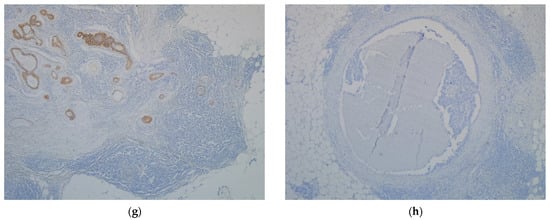

4.3. Immunohistochemistry